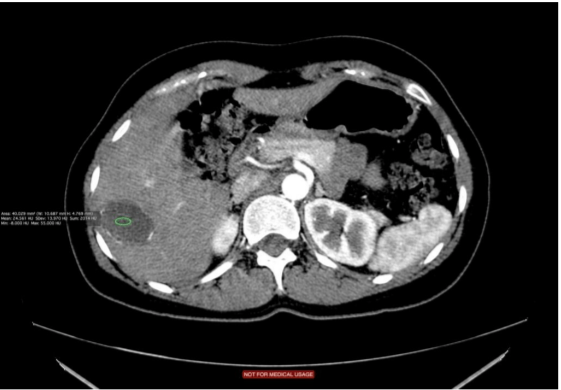

Na tomografia de abdômen com uso de contraste, são analisadas as estruturas vasculares da região estudada. A solução de contraste iodado é administrada por via endovenosa e distribui o contraste entre as estruturas com fluxos sanguíneos, realçando as estruturas hipervascularizadas, mostrando, por exemplo, tumores ou processos inflamatórios.